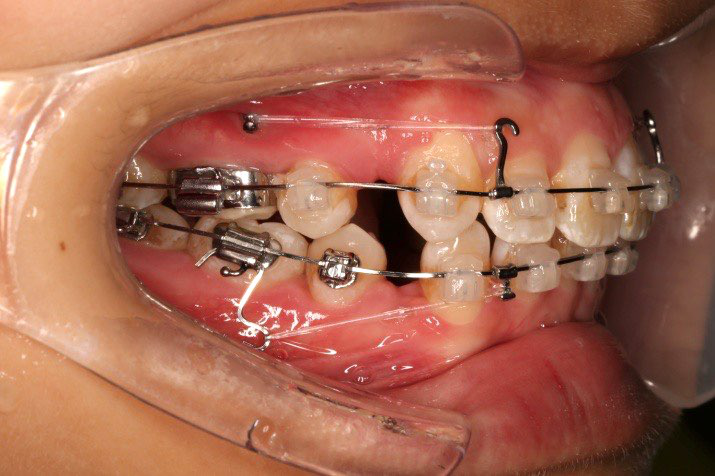

2016.10.31  初戴,0.013cu-niti2017.1.13  上颌加TPA,U56间斜形植入韩国庆北1312-08种植钉,上下0.16cu-niti

2017.02.16  上下0.014*25 cu-niti,50g 拉尖牙远中

2017.04.28

2017.04.28  上0.016*25ss 13、23近远中约5度 v形曲,下0.017*25ss

2017.05.26  磨牙近中倾斜,下颌36、46加power arm

2017.07.25

2017.07.25  上前牙加颈部弹力线